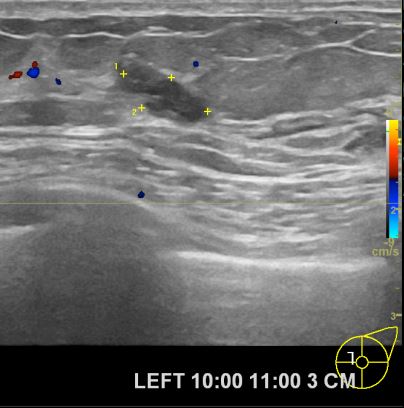

상기환자 외부검사상 이상소견으로 조직검사권유 받아 내원하신 70대 여성분으로

좌측 유방 조직검사 진행해 유방암 진단되었읍니다.빠른 쾌유를 바랍니다